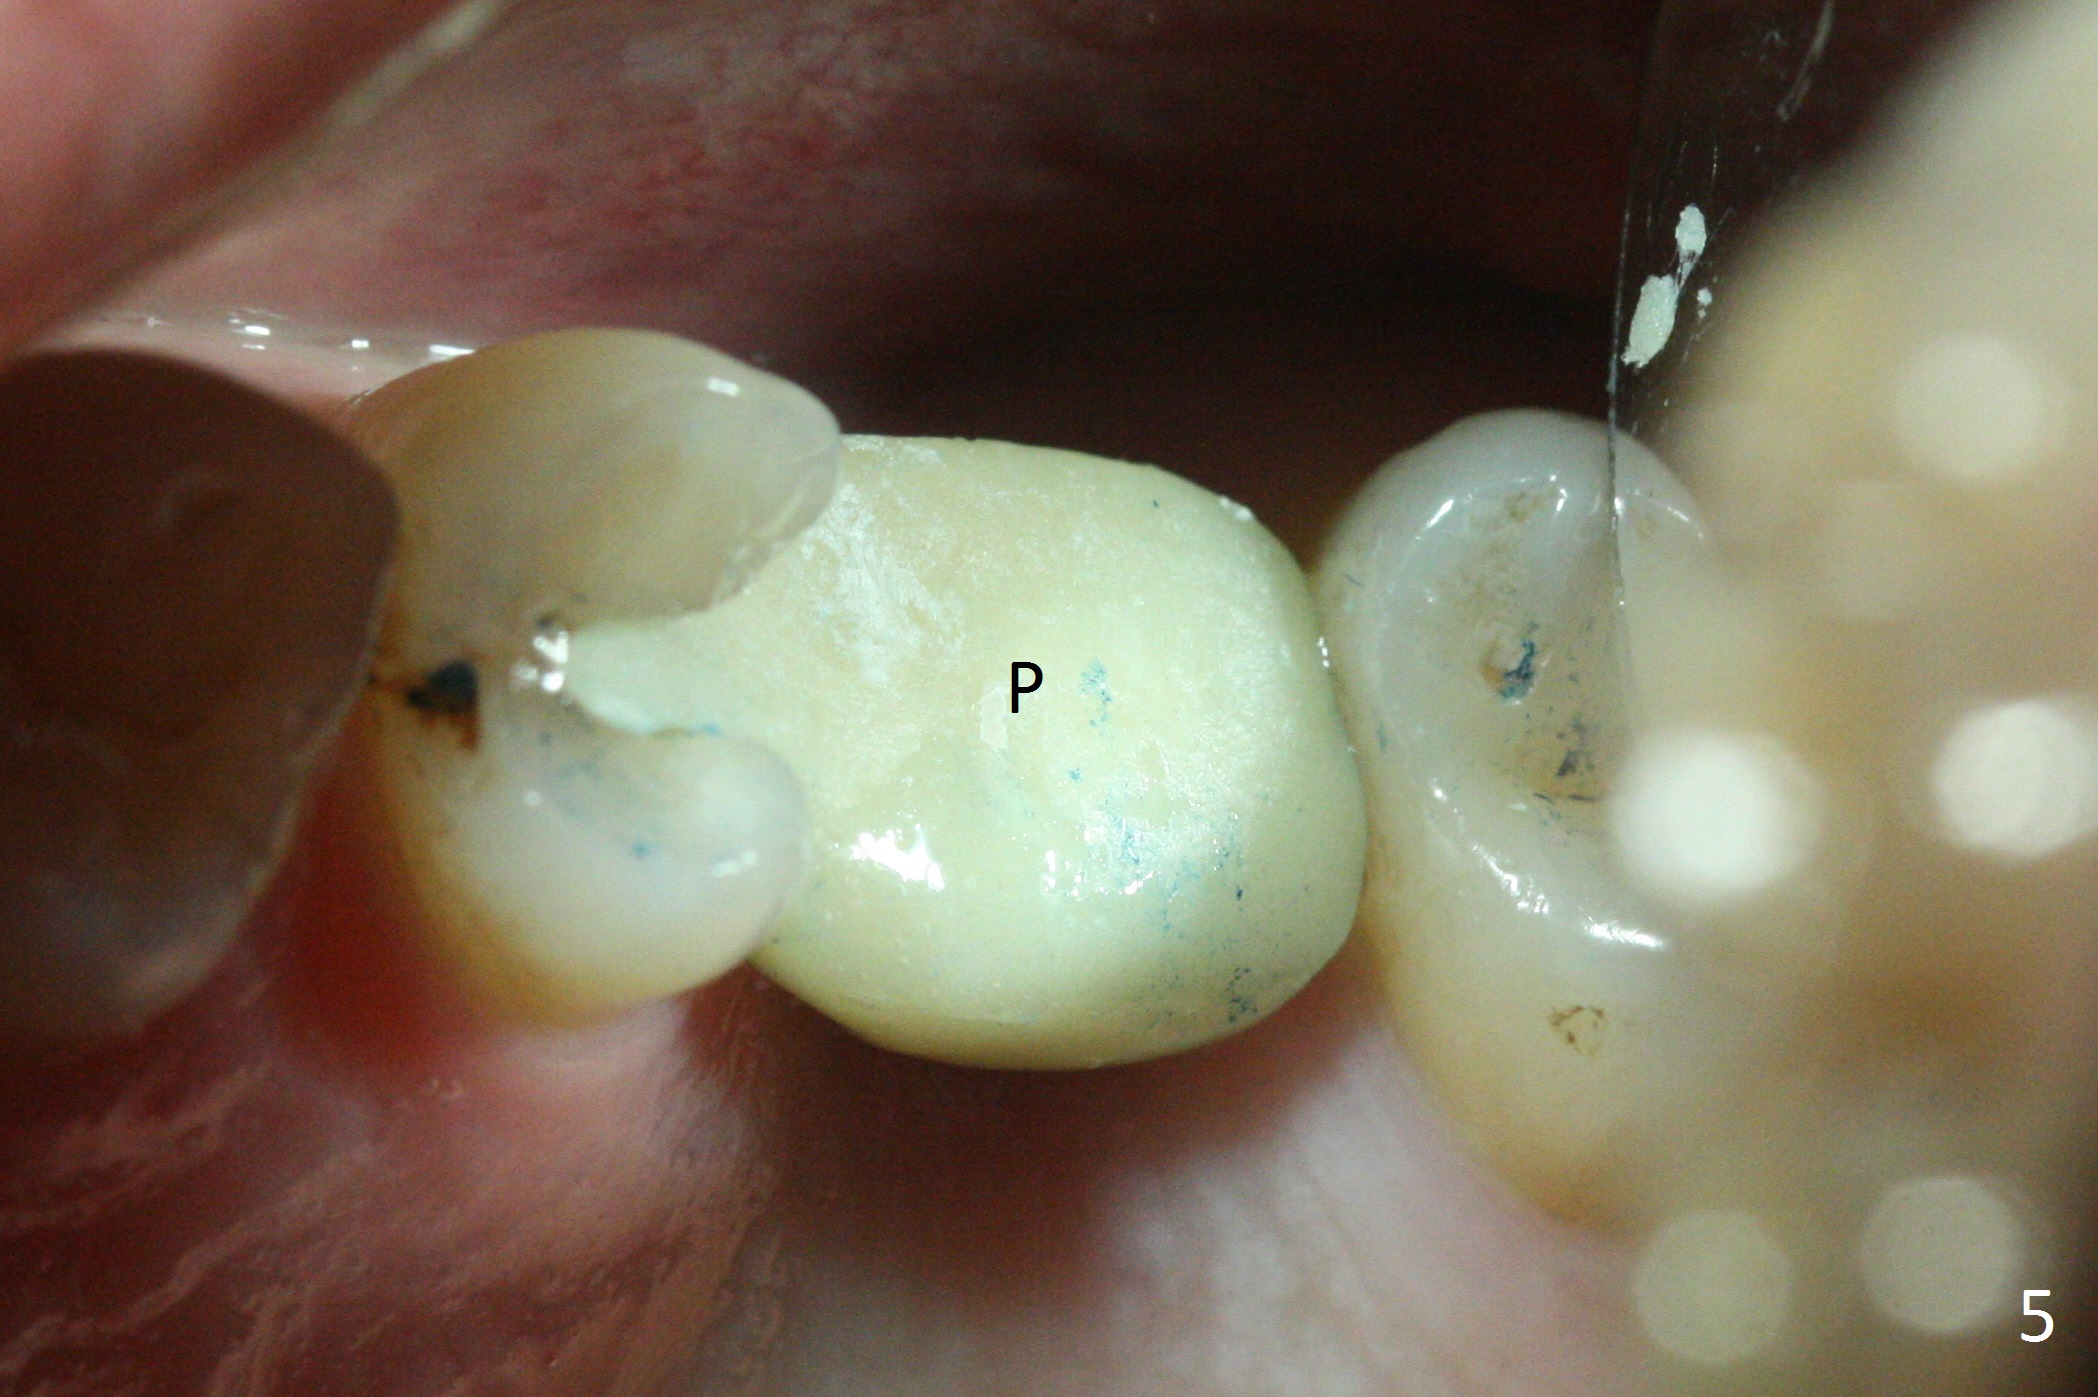

While the base of the ridge at #14 is wide, the top is moderate. IBS Magic Split is applied to gain access and test bone density (flapless). In fact the bone is hard. A 1.6 mm pilot drill is used for 9 mm (gingival level), followed by insertion of a parallel pin (Fig.1). Following Magic Expander 3.0 mm and Magic Drill 3.8 mm for ~ 11 mm (with empty feeling without air leak), a 4x11 mm dummy implant is placed with 25 Ncm (Fig.2). After insertion of a 4.5x11 mm dummy implant at 9 mm (35 Ncm; for further bone expansion), one piece of PRF plug and 1 piece of PRF membrane are pushed into the osteotomy, followed by allograft mixed with autogenous bone for sinus lift and placement of a 5x9 mm implant (Fig.3,4 with insertion torque >50 Ncm). A 6x4(2) mm abutment is placed for fabrication of an immediate provisional (Fig.5 P). There is no nasal hemorrhage postop. PRF membrane and plug are used to prevent and repair sinus membrane perforation and facilitate wound healing. There is mild bone resorption at the crest 11 months postop (Fig.6,7). The bone resorption seems to be worse 8 months post cementation (Fig.8,9); in fact the abutment screw is loose.